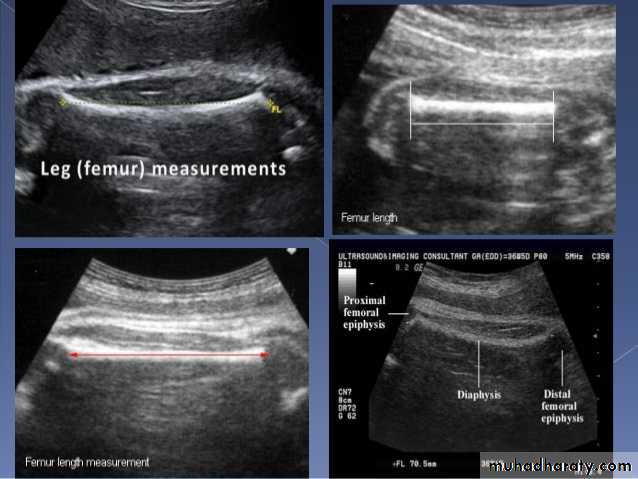

BPD together with head circumference (HC), abdominal circumference (AC), and femur length (FL) are computed to produce an estimate of fetal weight. In the second trimester this may be extrapolated to an estimate of gestational age and an estimated due date (EDD) .